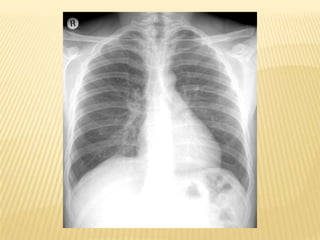

Assessment and diagnosisChest radiographSputum Gram stain and cultureDiagnostic bronchoscopyCBC with differential countChemistry panelBlood culturesABG

Assessment and diagnosisChestradiographSputum Gram stain and cultureDiagnostic bronchoscopyCBC with differential countChemistry panelBlood culturesABG